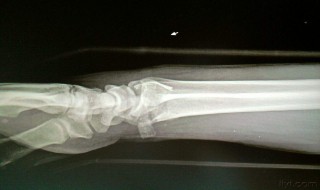

1、评不上残是因为骨折情况没有达到评级的标准。

2、虽然一般来说骨折都能评定伤残等级,但是骨折并不是工伤评级的主要依据。工伤评级是有规定的标准的,是需要进行工伤鉴定。若进行工伤鉴定后,证明其确实存在功能障碍或者残疾,才会评级。

3、工伤职工对伤残等级结论不服,可以通过由下而上的复查程序,以保障鉴定工作的公正合理。譬如职工对市劳动能力鉴定委员会作出的伤残鉴定结论不服的,可以申请省级劳动能力鉴定委员会进行再次鉴定,最后省级劳动能力鉴定委员会作出的鉴定结论为最终结论